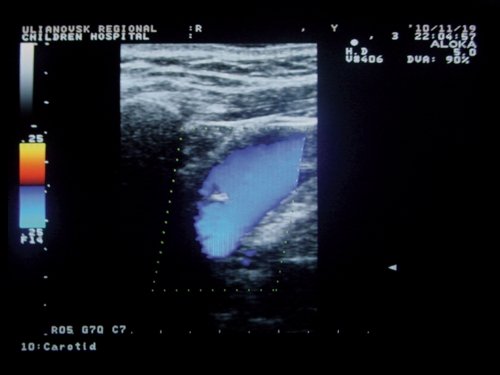

Оценка гемодинамики на пятом уровне показала увеличение площади просвета ВЯВ у больных ГЭ [1,07 (0,81) см2] по сравнению с контролем [0,82 (0,29) см2; p<0,05]. В то же время у 23 (24,7%) больных с конституциональной флебопатией были выявлены гипоплазированные и малые вены (рис. 5).

Рис. 5. Гипоплазия внутренней яремной вены у больного с конституциональной венозной недостаточностью.

Обязательным условием нормальной венозной гемодинамики является сохранность функции клапанного аппарата ВЯВ [11-13, 16]. По нашим наблюдениям, при исследовании в горизонтальном положении у 100% больных с КФП была выявлена клапанная недостаточность вен различной этиологии: у 55 (67,9%) - врожденные аномалии клапанов, их недоразвитие либо отсутствие, у 7 (8,6%) - тромбозы, у 19 (23,5%) - вторичная клапанная недостаточность в результате расширения ВЯВ. У 8 (9,9%) пациентов клапанная недостаточность сочеталась со сдавлением ВЯВ извитыми ОСА. У 72,8% больных с КФП недостаточность остальных клапанов ВЯВ была гемодинамически значимой: сопровождалась подклапанной регургитацией и ретроградным забросом крови, усиливавшимся при пробе Вальсальвы. У 27,2% обследованных регургитация возникала только при проведении пробы Вальсальвы, что указывает на клапанную недостаточность функционального характера (рис. 6, 7).

У пациентов с гипертонической энцефалопатией при всех клинических вариантах течения заболевания отмечается расширение ВЯВ в области нижней луковицы, что можно рассматривать как необратимые нарушения венозной циркуляции, возникающие вследствие повышенной нагрузки объемом при артериальной гипертонии. Выявленные наряду с этим аномалии строения брахиоцефальных вен в группе с КФП значительно ограничивают резерв венозного оттока, что может приводить к клинической декомпенсации при повышении артериального притока, при нарушении центральных механизмов венозного оттока, при присоединении патологии контралатеральной вены [13]. Снижение линейных и увеличение объемных параметров кровотока по ВЯВ у больных с КФП могут свидетельствовать о наличии венозного застоя у больных данной группы на фоне веногипотонии.